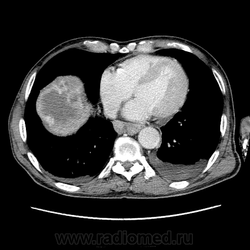

Здравствуйте, коллеги! Мужчина около 70 лет. Жалобы: слабость, утомляемость около 3х месяцев, чувство тяжести на желудке после еды. Анамнез: онко не было. С вышеописанными жалобами обратился ко врачу, сделали ФГЭДС - признаки гастродуоденита, по биопсии - N. В течение 2х последних недель существенно похудел и начал желтеть. Выполнена МСКТ

Вероятно ГЦР, со всеми последствиями.

А как насчет холангиокарциномы с тромбозом воротной вены и мтс в средостение, лимфоузлы брюшной полости и забрюшинного пр-ва?

Внимательно пересмотрел, признаков характерных для ГЦР не нашел (кроме тромбоза). Согласен с холангиокарциномой, ещё бы отсроченную фазу, для печени минут через 12-15 .

1. Гиперденсивность, в артериальную фазу  всей опухолевой массы (опухоль хорошо васкуляризирована)

2. Гиподенсивность, в портальную фазу (быстрое вымивание, опять же обусловлено васкуляризацией)

3.Тромбоз портальной вены.

Для холангиокарциномы характерно гиперденсивность, в отсроченную фазу, за счет аффинитета к контрастному веществу.